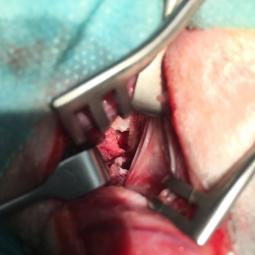

Trépanation de la bulle per-opératoire

La trépanation de la bulle tympanique: cas particulier des polypes naso-pharyngiens

Ces polypes se forment, chez les chats,  au niveau du rhino-pharynx, se prolongent dans la trompe d'Eustache (trompe auditive) et se retrouvent dans la bulle tympanique. Leur ablation est minutieuse et n'est pas sans risque...

Leur cause est souvent d'origine inflammatoire suite à un coryza chronique pas exemple.